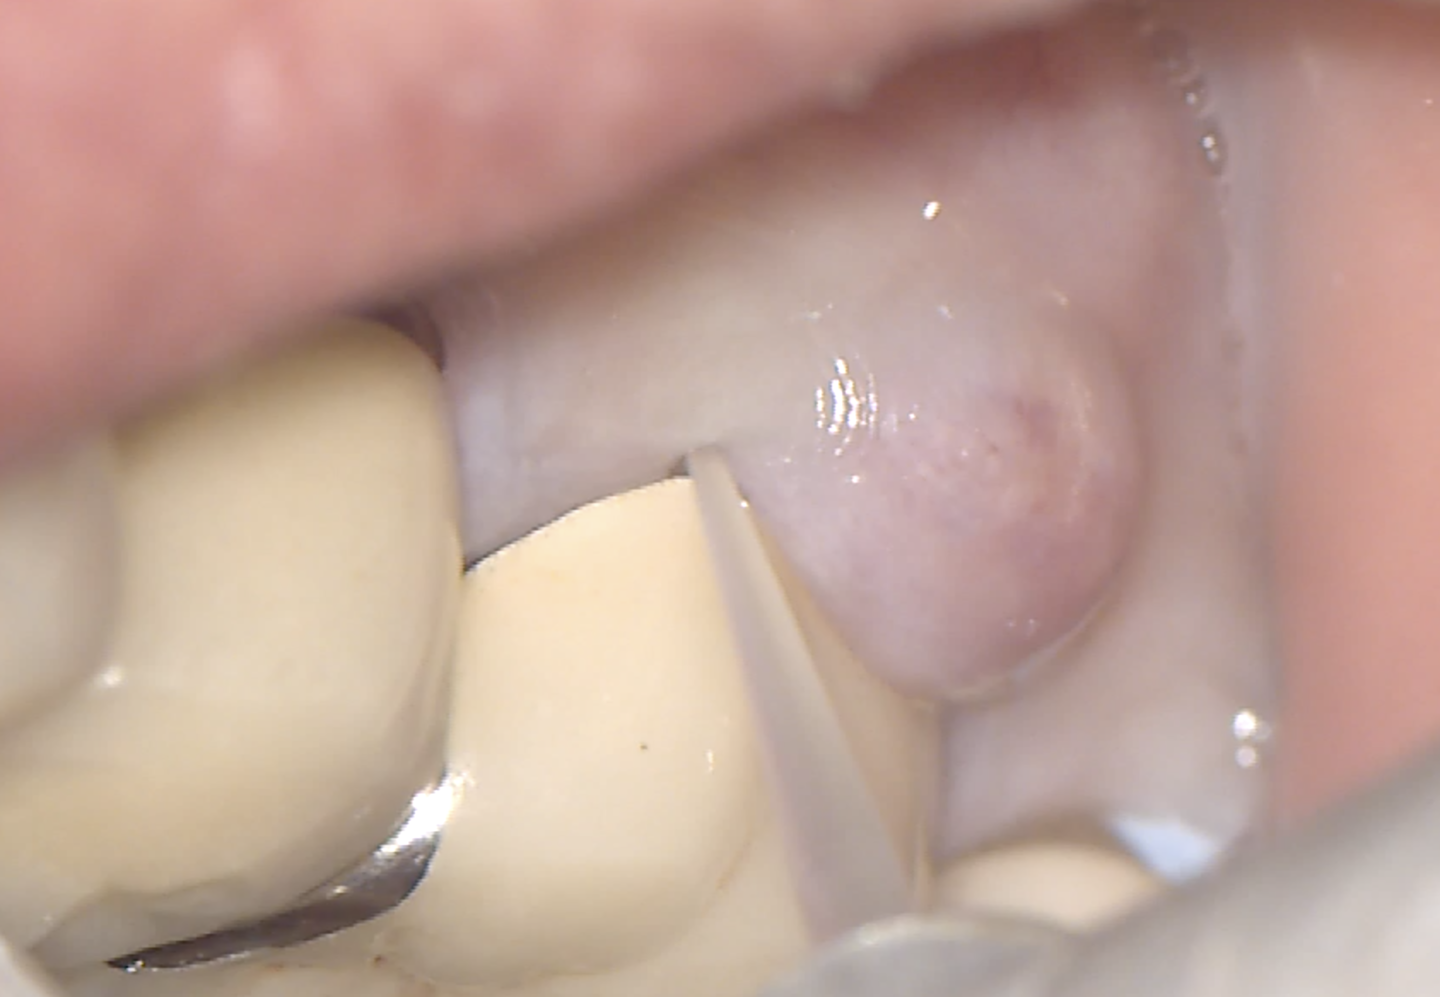

インプラント周囲粘膜炎:はぐきの炎症

・インプラントの周りのはぐきが赤く腫れる

・歯ぐきがなんとなくぶよぶよ

・歯みがきやフロスで出血する

・違和感がなく自覚症状がない場合がある